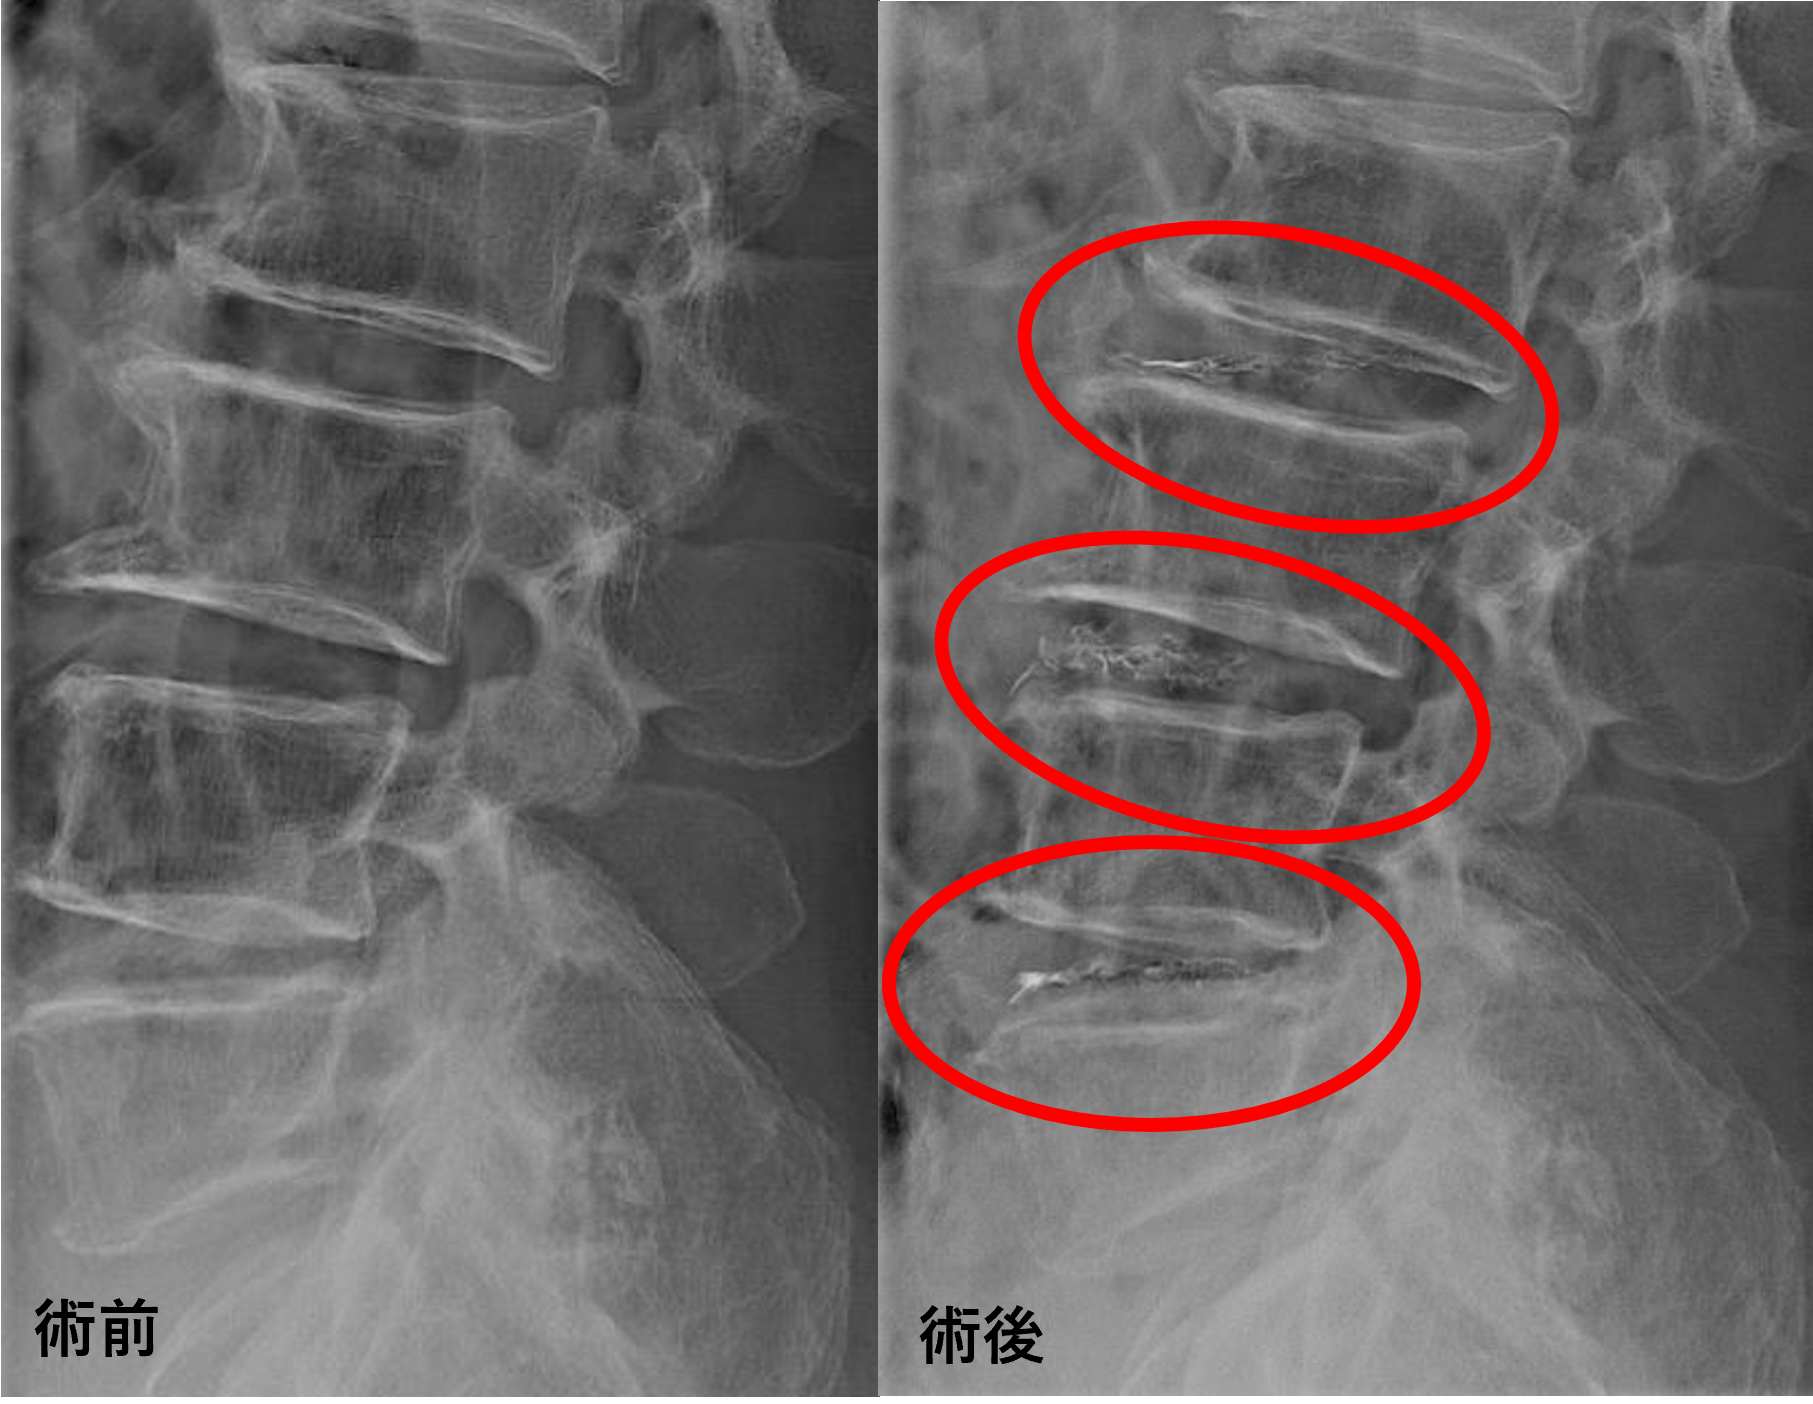

画像及び所見について

- L2/3 – 椎間板変性

- L3/4、4/5 – 椎間板変性、脊柱管狭窄

以上のことが画像上認められました。

L2/3、3/4、4/5の椎間板所見による脊柱管の圧排が、症状の原因の可能性が高い。

患者様と相談の元、L2/3、3/4、4/5にセルゲル法を施行